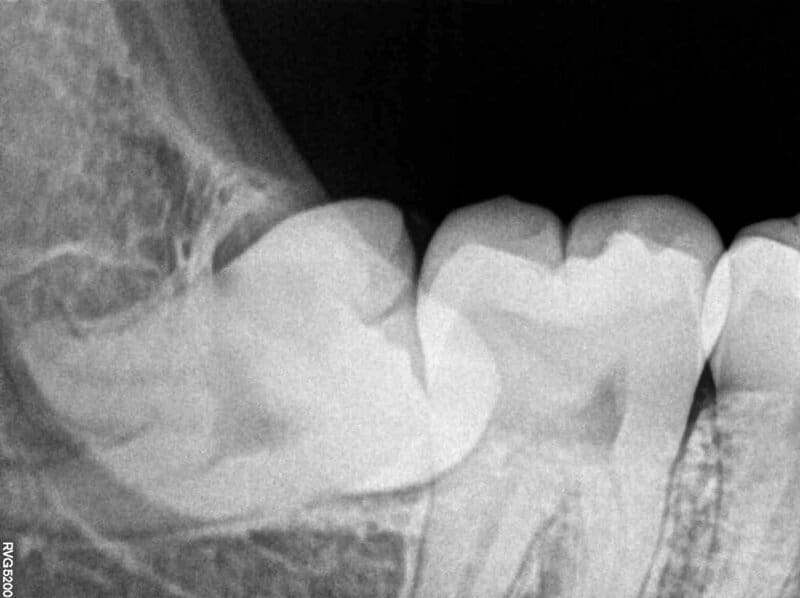

Dental x-ray of impacted lower left wisdom tooth with a horizontal orientation. Source: Wikipedia

As human diets shifted from tough, raw foods to softer, cooked meals, the jaw size decreased, leading to insufficient space for third molars, or wisdom teeth. This reduction in jaw size, coupled with the prevalence of soft, processed foods, has resulted in dental issues such as impacted wisdom teeth and malocclusion. Studies indicate that approximately 50% of individuals in industrialized societies have their wisdom teeth removed due to these complications. (centraljerseydental.com)